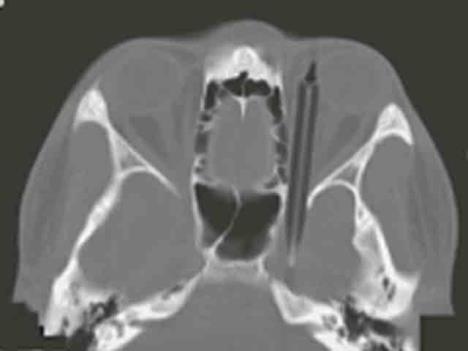

Skenerom je utvrđeno da je u sinusima imao 10 centimetara dugu olovku koja mu je povredila desnu očnu duplju

Kako prenosi AP, 24-godišnji muškarac iz Avganistana zatražio je pomoć u bolnici u Ahenu pošto je rekao da je godinama patio od glavobolja, konstantnih prehlada i slabovidosti. Skenerom je utvrđeno da je u sinusima imao 10 centimetara dugu olovku koja mu je povredila desnu očnu duplju.